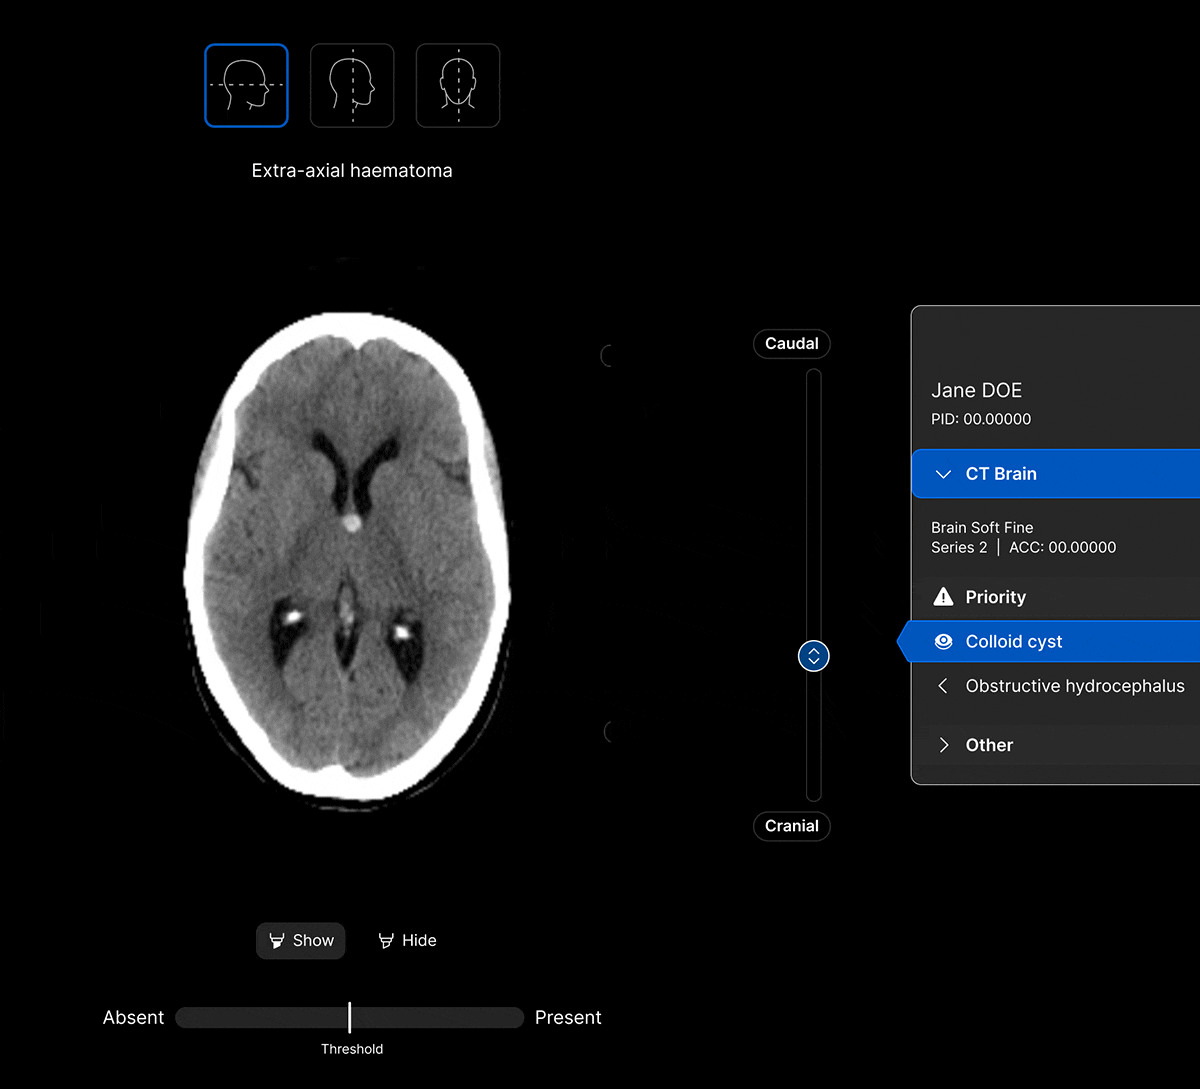

The UI integrates seamlessly with PACS/ RIS, displaying a resizable, no-click overlay window with findings and localisation.

Customisable features.

Customisable thresholds, for individual findings (to optimise for sensitivity / specificity) to tailor the workflow to your clinical setting or population.

Identifies up to 130 suspected head CT findings, grouped by urgency or other customisable criteria.

Coloured overlays on the image to quickly locate findings.

Explainable AI feature to improve AI interpretability and improve clinical decision-making.

AI analysis viewable on different head CT slices.

View the findings in sagittal, axial and coronal projections.

View findings within preset subdural, bone, brain, soft tissue and stroke views to provide additional context to the AI results.